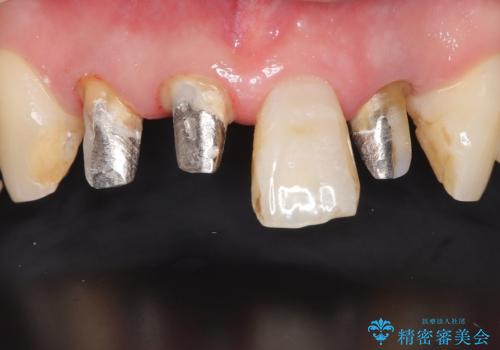

古い被せ物を除去しオールセラミッククラウンで治療を行いました。

被せ物の適合が悪く劣化もおこし色が変色している状態でした。そのため他の歯とも色が合っていませんでした。古い被せ物を除去し形を整えた後にオールセラミッククラウンで治療を行いました。

根っこの先端に病巣(根尖性歯周炎)があったため根管治療または抜歯してインプラントを提案しましたが、患者さんのご希望により被せ物の治療のみを行いました。